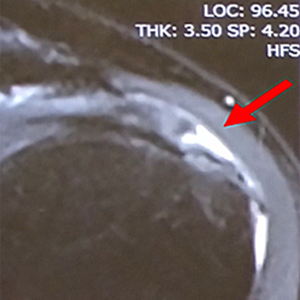

症例 2